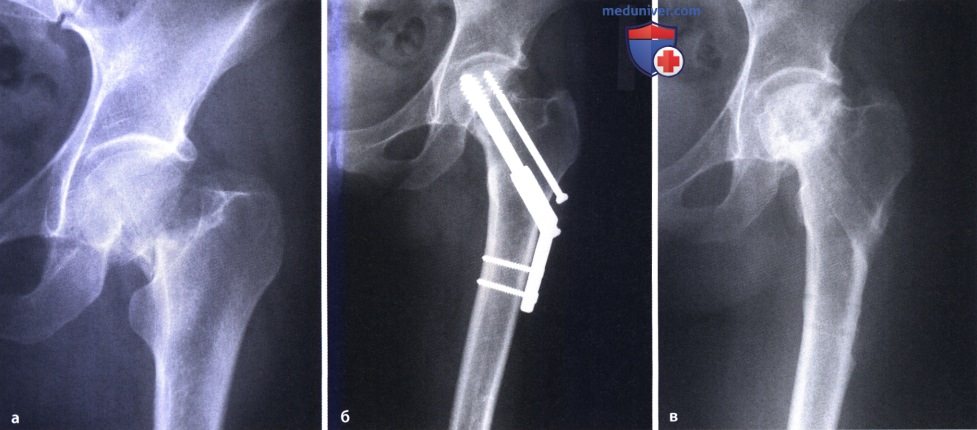

Диагностика ТБС рентгеном и асептический некроз: особенности лечения

Раздел: Снимки-откровения